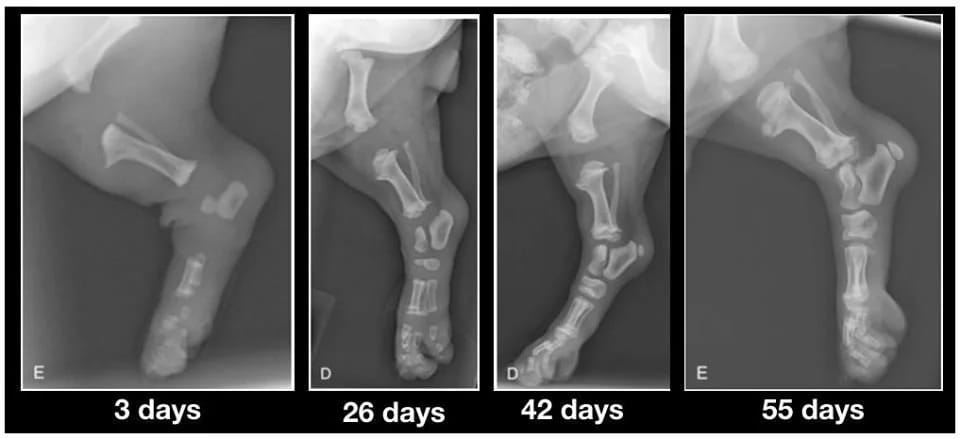

L’ossification

À la naissance, une grande partie du squelette est encore cartilagineuse. La solidification des os se fait progressivement au niveau des cartilages de croissance, situés aux extrémités des os longs.

Ces zones restent fragiles jusqu’à leur fermeture complète.

Tant que les cartilages de croissance sont actifs, le squelette est plus vulnérable aux contraintes excessives (sauts répétés, escaliers fréquents, activité sportive intensive).